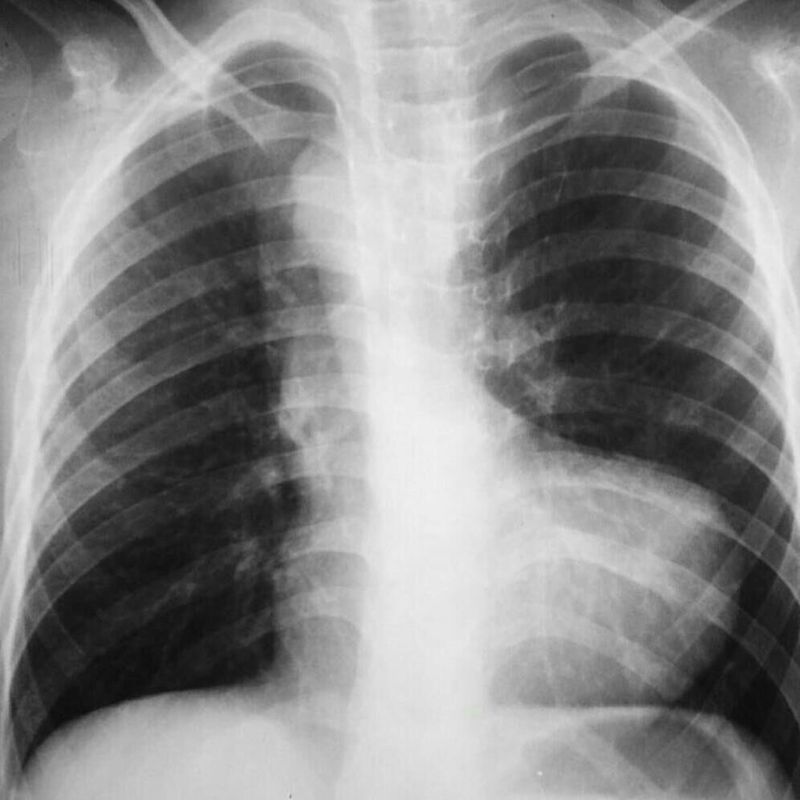

Diagnosis please

TOF